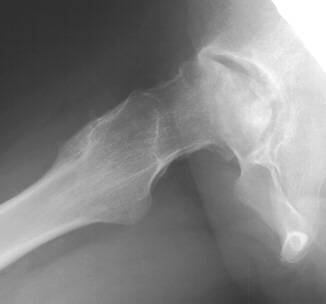

M.L. was diagnosed as having sickle cell anemia during early childhood.

She experienced two major crises each year, treated with hydration and

pain medication. She was first seen at age 9 following a crises with concomitant

left hip pain

Bone scan was also obtained which demonstrated a cold area. Treatment consisted

of activity restriction and partial wt. bearing.

F/U age 14 with a 2mo. history of left hip pain, aggravated with activity.

Clinical findings were not suggestive of infection. She was diagnosed with

AVN of the left femoral head. Management consisted of NSAIDS, restricted

wt. bearing.

Two months later she under went a left hip core decompression and bone

grafting without problem

Rehabilitation was steady maintaining a restriction on wt. bearing and

encouraging range of motion. She had a significant decrease in her pain

although the radiographs showed progressive collapse.

Four years later, she is able to ambulate without any aids but complains

of a dull ache in her left hip and a limitation in rotation

.